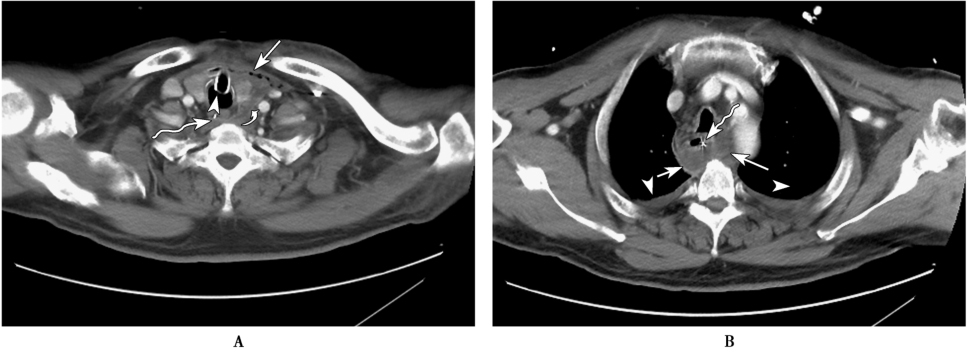

纵隔脓肿是一种发展迅速的致死性疾病,病死率高达40%~50%。纵隔中上段脓肿形成主要是牙源性感染、咽旁隙及咽后隙感染下行或是上段食管损伤及中上纵隔感染本身引起;下纵隔脓肿形成主要源于下段食管损伤,常并发单侧或双侧胸腔感染。纵隔脓肿X线检查可表现为向一侧或双侧纵隔突出的阴影,若与气管或食管相通则可出现气-液平面;CT可清晰显示纵隔脓肿的部位、范围、脓肿壁、气-液平面及其与周围结构的关系,增强扫描可见脓肿壁强化(图2);MRI增强检查亦可见脓肿壁明显强化。

图2 纵隔脓肿

患者,男,58岁,发热1周。A.胸部CT增强扫描纵隔窗示甲状腺左叶左旁与左侧颈总动脉间(白弯箭)液性渗出影,纵隔内多发游离气体密度影(白箭),气管(白箭头)及食管内(波浪箭)分别见插管影;B.胸部CT增强扫描纵隔窗示食管左侧及后方(白箭)包裹性液性渗出影,囊壁轻度强化,食管内(波浪箭)见置管影,双侧胸腔内少量积液(白箭头)。